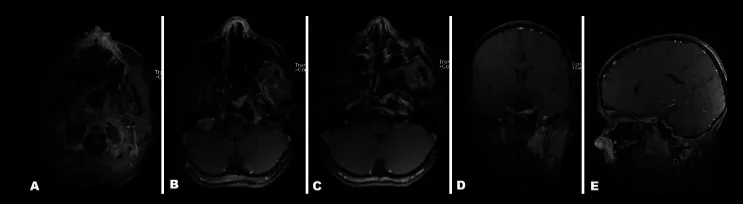

术后1天,骨肿瘤部分几乎全部切除

术后13个月,全身MRI复查显示,女儿病情未复发,无论是原发病灶还是脊髓,均未发现其他具有LCH特征性的病灶。

术后32个月,女儿的状况持续良好,不仅肿瘤无复发,也未出现其他新发的骨质病变。

手术及化疗后32个月MRI显示病灶完全缓解